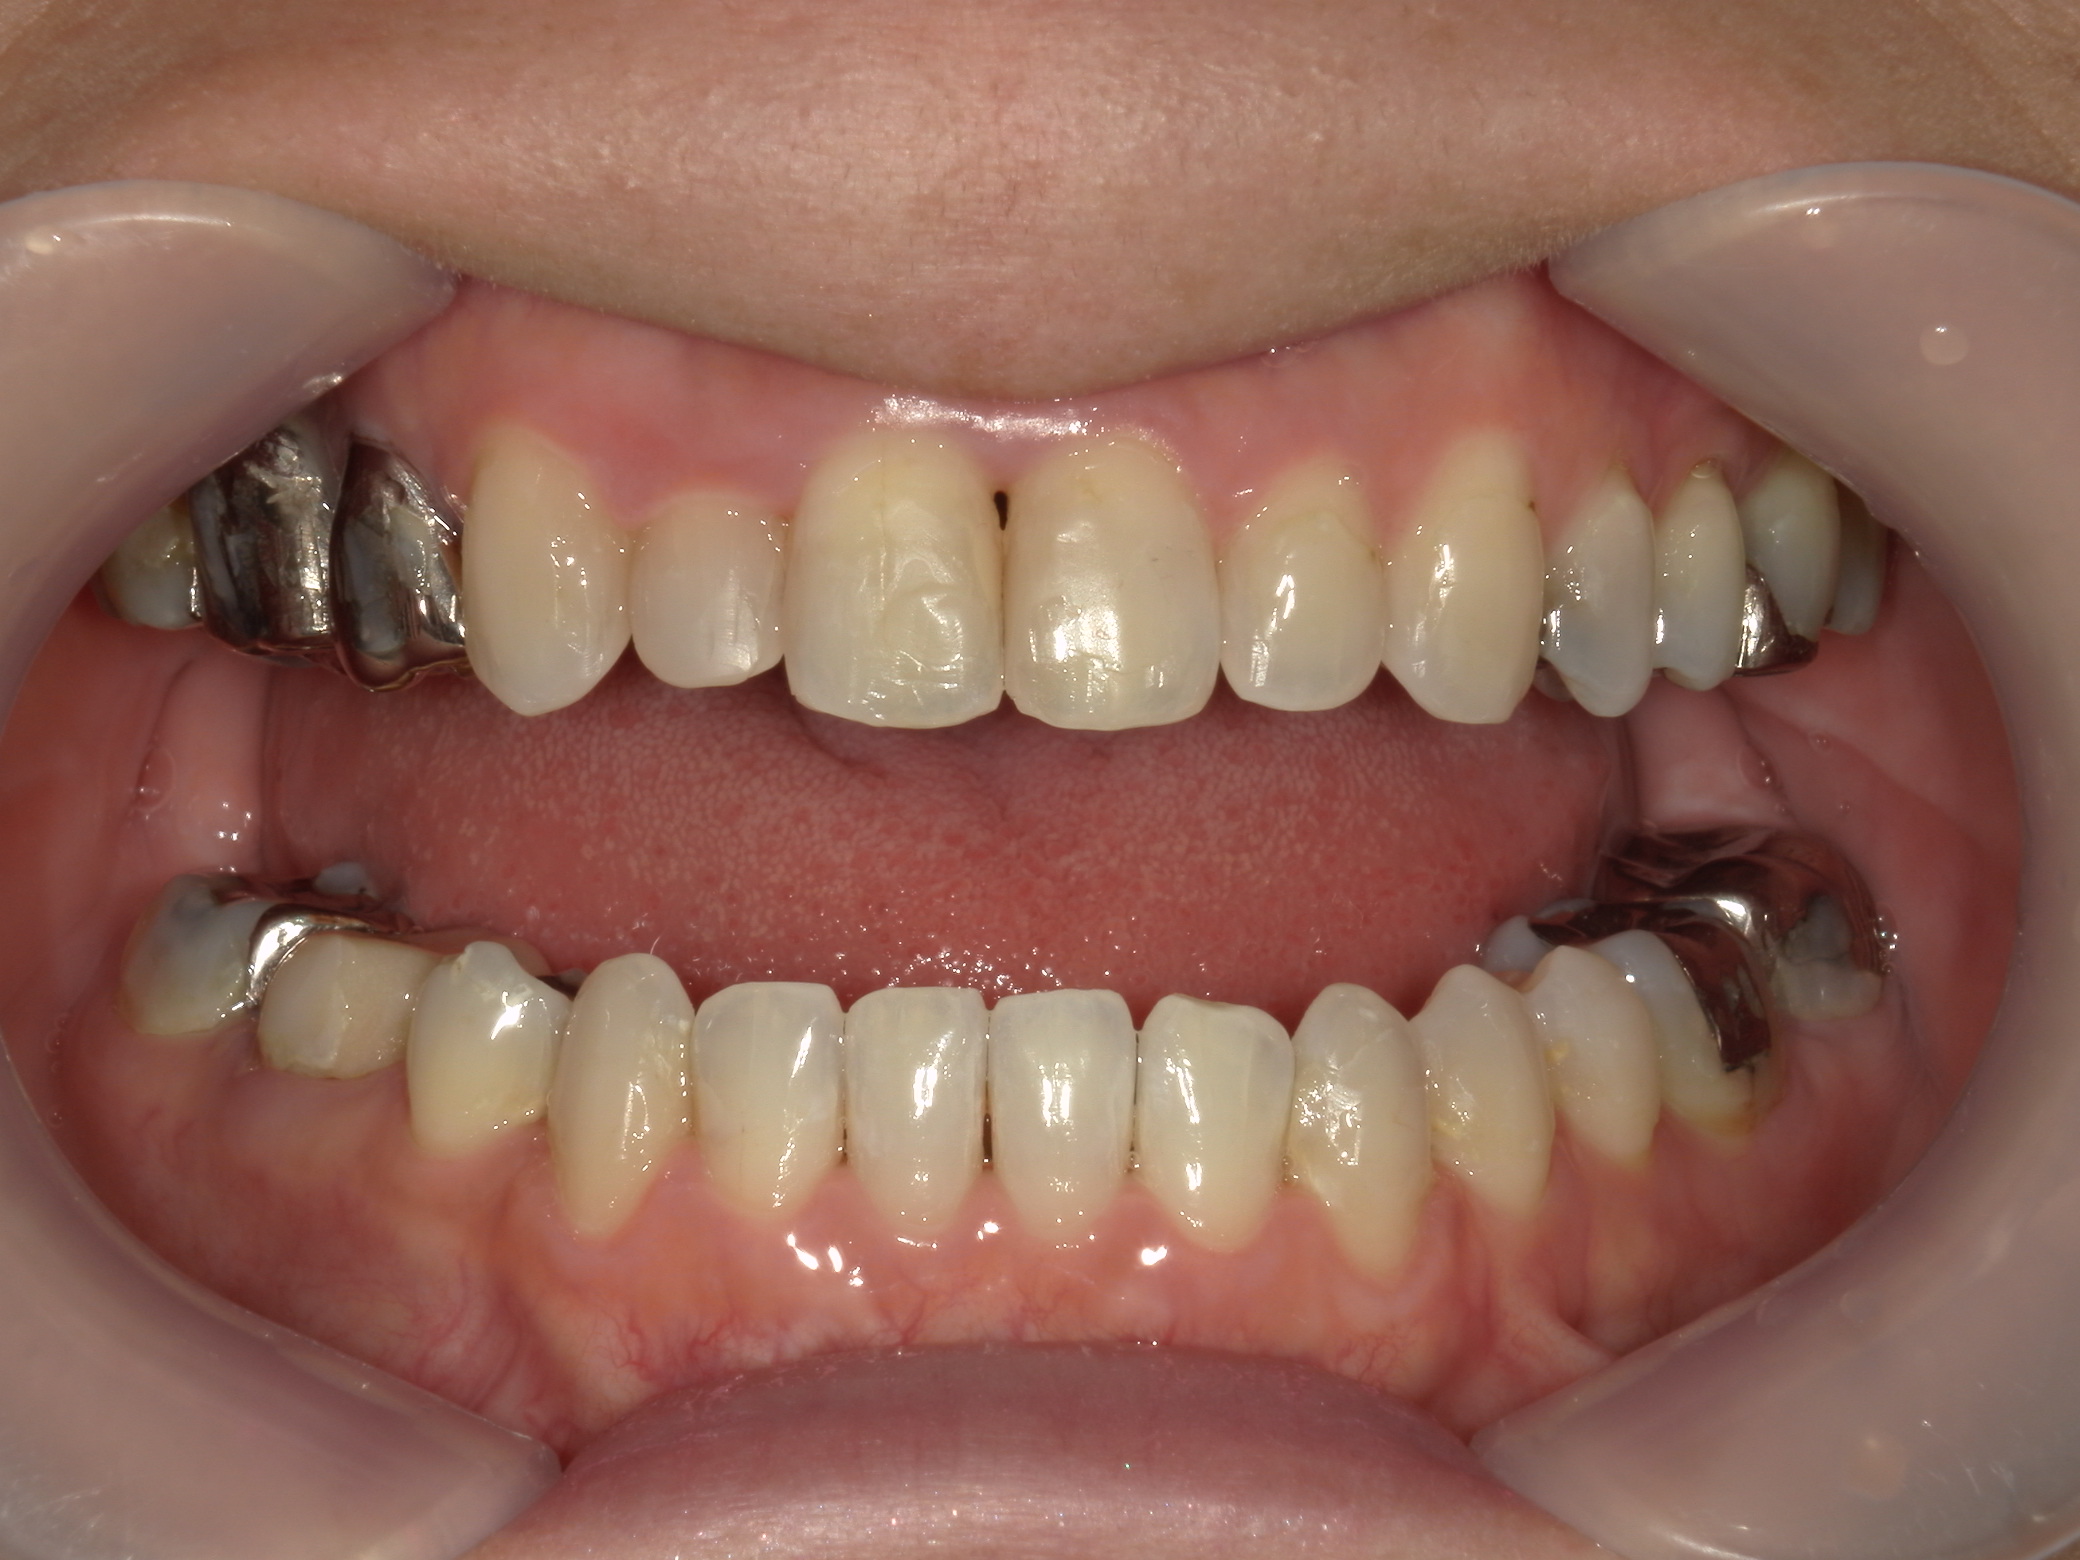

インビザライン矯正 症例(30)

主訴: 受け口、歯並びが気になる。

①患者様はインビザライン矯正をご希望でしたが、上顎骨が小さく、受け口になっているので、インビザライン矯正で治療するために「骨切断OPE」「矯正装置(MSE+フェイスマスク)」で上顎骨を拡大しました。

②右上前歯が内側に入っているため、歯列に入る隙間を作るためにワイヤー矯正を併用し、右上前歯を出しました。

③矯正装置を除去し、インビザライン矯正で歯列を整えました。